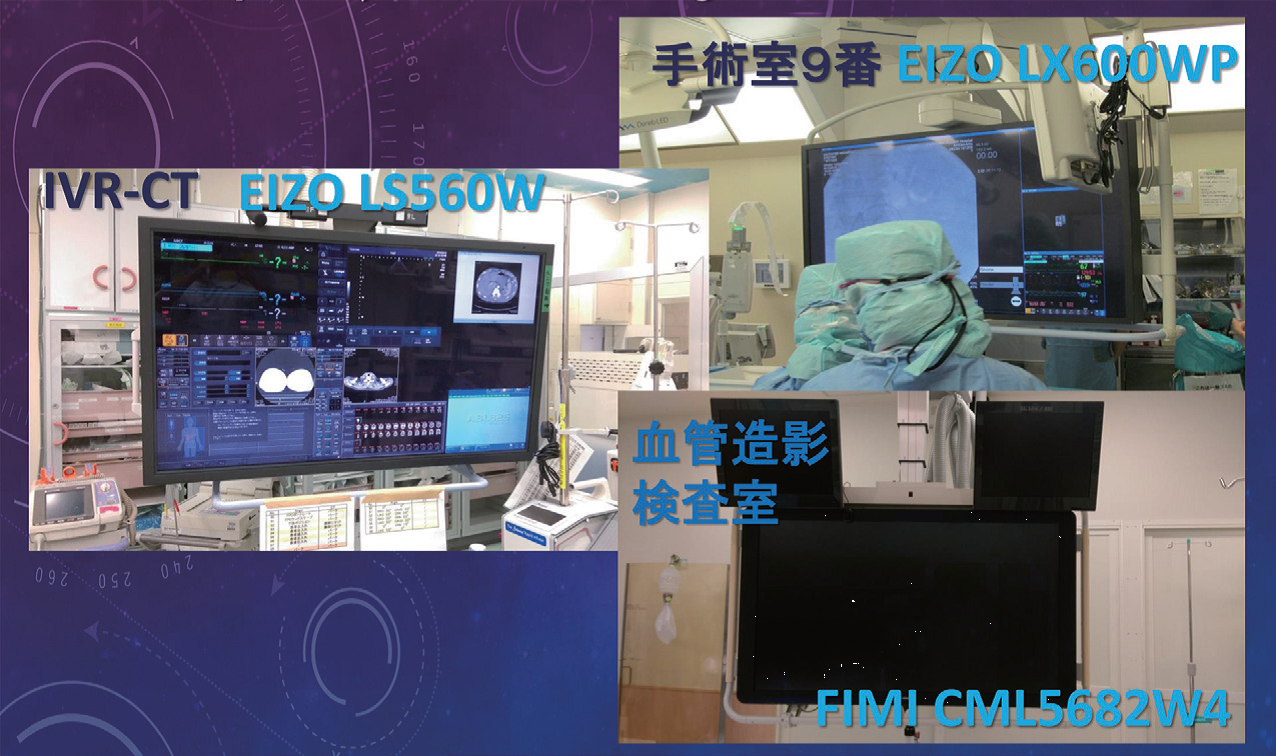

手術室9番にEIZO LX600WP、

IVR-CTにEIZO LS560W、

血管造影検査室にFIMI CML5682W4が

設置されている。

大型モニタの有用性と当院における大型モニタの比較

大型モニタの有用性というと、画像が大きいことと、画面が大きいことが挙げられる。

画像が大きいということは、細かいワイヤや細いデバイスが見やすく、より多くの医師が見ることができ、より安全に早く手技が行えることにつながる。画面が大きいということは、マルチモニタとしての有用性があることで、画像から視線をそらすことなく、多くの情報を得ることができる。また、手術室ではインジェクター、支柱台、電気メスなどがあってモニタを引き寄せられないことがあるが、ある程度距離があっても画像を十分観察することができる。

今回、当院にある3台の4×2K大型モニタであるEIZO LX600WP(60インチ)、EIZO LS560W(56インチ)、FIMI CML5682W4(56インチ)、およびSYNAPSE Viewer2Mの濃度、輝度、特性を比較してみた(図1)。各モニタにより特性曲線が異なっており、EIZOのモニタでは直線階調が用いられており、FIMIではX線フィルムに近い非線形の階調が用いられていた。最高黒レベルにも差がありLS560WとLX600WPはそれぞれDensity:2.4

とDensity:2.6、FIMICML 5682W4とSYNAPSE Viewer2MではDensity:3.0であった(図2)。